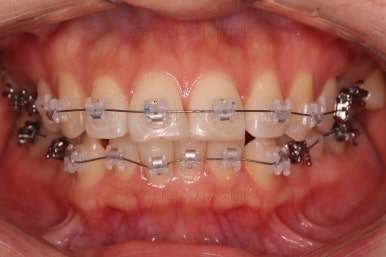

마찬가지로 부산연산동교정치과 초진 시 입안의 모습입니다.

눈에 띄는 것은 윗니 안쪽 치아 하나가 아예 입천장쪽으로 나서 매우 삐뚤어요.

저렇게 삼각혁으로 배치되어 있는 치아는 셋 중 하나는 꼭 썩어요.

셋 사이에 음식물이 잘 끼고 양치가 힘들기 때문이죠.

아래 앞니도 삐뚤한 편이었고 아래 앞니가 불쑥 위로 올라와 있어서 이를 악 다물면 위아래 앞니가 많이 겹치는 "과개교합" 패턴이 나타나요.

윗니가 전반적으로 아랫니보다 앞에 나와 있어서 2급 부정교합에 윗니만 튀어나온 양상이고 이 때문에 윗니 앞니가 다치고 부러졌따가 떼운 흔적이 보이네요.